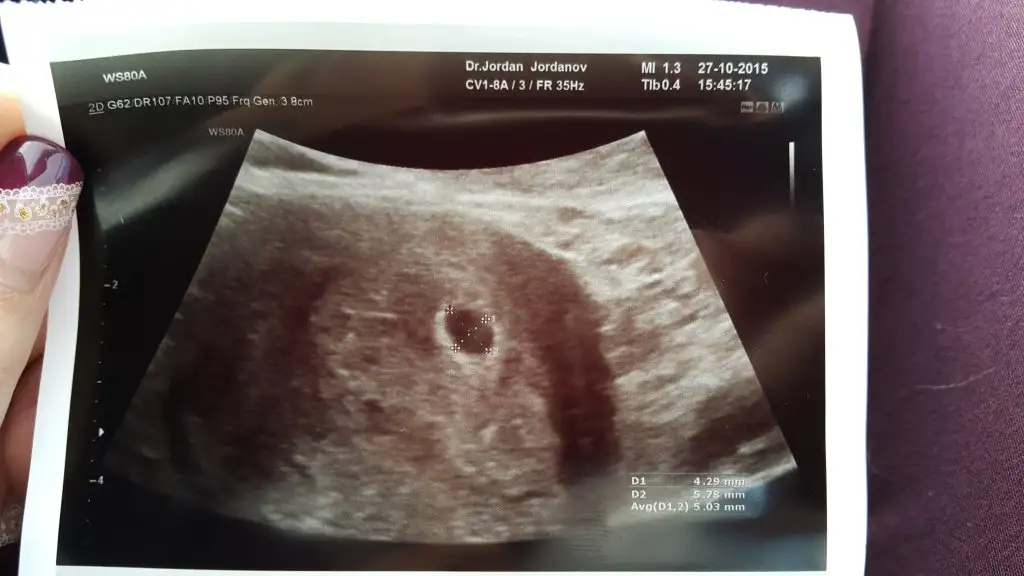

Gittim. 5 haftalık falansın daha küçük falan dedi. 2 hafta sonra tekrar çagırdı. Ama benim icim hic rahat degil. Yine bur sorun var sanirim. Lutfen fotoya bi bakip 5 haftalik icin santim milim uyuyormu die bakarmisinız. Cok moralim bozuk ve endişeliyim nedense

Eklentiler

• 20151027_145511.webp

20151027_145511.webp

31,4 KB · Görüntüleme: 194

Canimm gayet normal bence

Kendimin 5 haftalik kese gorüntüsüyle karsılastırdim. Ki o zaman bebek ya da yolk kesesi görmemistik. 0.78 cm yani 7mm imis ama 5+4 te. Bence seninde normal. Hicc endiselemme;)